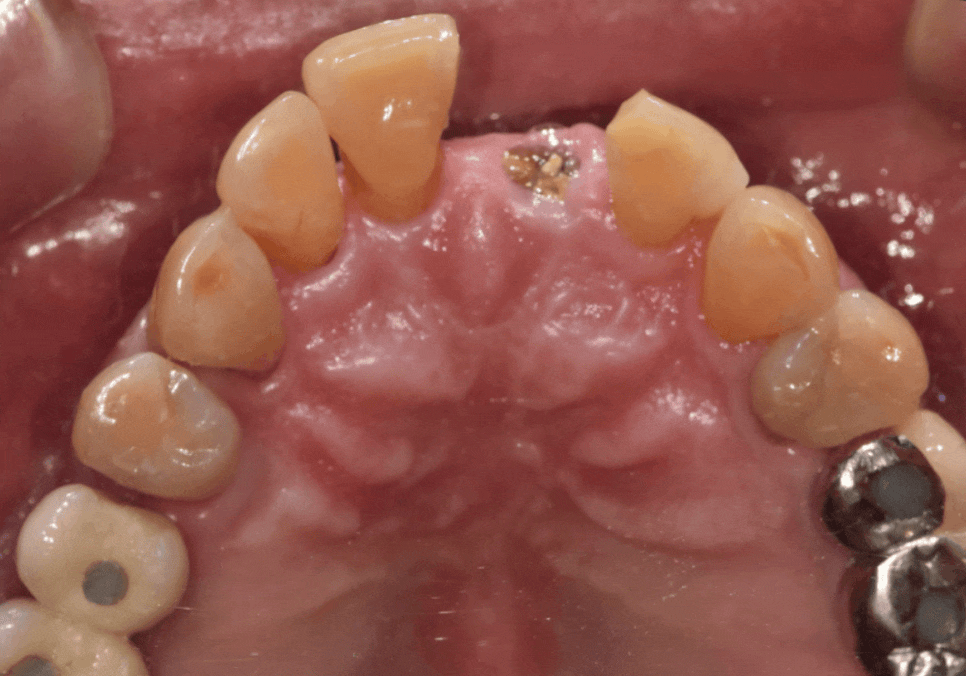

이 환자분은

왼쪽 앞니가 충치로 인해 부러지면서

내원하셨습니다.

겉으로 보면

앞니 하나만 문제가 있어 보일 수 있지만,

입안을 자세히 살펴보니

앞니 4개 모두 흔들림이 있었고

잇몸뼈 높이도 많이 낮아져

있는 상태였습니다.